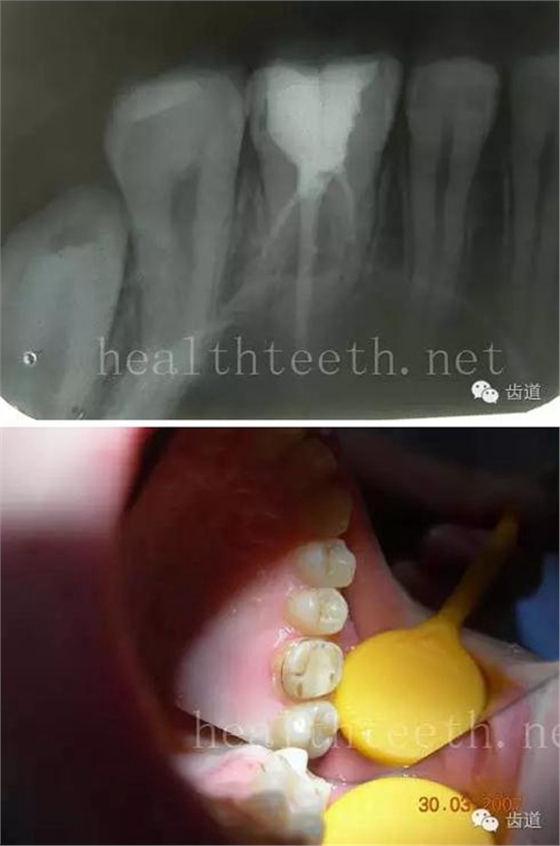

長期戴活動義齒不當或是戴不良修復(fù)義齒造成的口腔粘膜潰瘍,應(yīng)該引起高度警惕,因為這種潰瘍?nèi)菀装┳?/span> 黑毛舌 舌息肉,該患者同時伴有胃、食管息肉,后來看內(nèi)科了,具體情況不詳 四、孩子的牙齒問題 乳牙未退,牙根穿出牙齦對上唇粘膜造成刺激 乳牙滯留,也是孩子在退牙過程中最容易遇到的問題 五、牙齒發(fā)育上的問題 變色牙 氟斑牙 釉質(zhì)發(fā)育不全 四環(huán)素牙 牙神經(jīng)治療后的牙齒變色 10歲孩子剛剛萌出的牙齒變色 2、埋伏牙 左上乳3滯留,恒3未見萌出,曲面斷層片顯示牙齒埋伏 通過CT片確定埋伏牙齒具體的位置,顯示距離左側(cè)上頜竇很近,偏唇側(cè),這為手術(shù)定位提供了方便 手術(shù)中切斷、完整拔出,未損傷上頜竇 其他埋伏牙 3、多生牙 病例1 病例2 病例3,同時多生兩顆牙齒 4、各種畸形牙 畸形過小牙 融合牙:恒牙和乳牙都可以發(fā)生融合的情況(兩顆牙齒長在了一起) 畸形中央尖:在牙齒的中央,兩個牙尖之間又多長出一個牙尖,由于進食的磨耗很容易造成磨穿,神經(jīng)就會與外界相通,出現(xiàn)牙髓炎的癥狀 六、牙齒的外傷 牙冠折斷 牙根折斷 烤瓷牙打樁修復(fù)后牙根折斷 外傷后牙齒的全脫位,應(yīng)該保留牙齒盡早做再植手術(shù) 七、牙齒的慢性損傷 牙頸部楔狀缺損 牙冠劈裂及完整拔除后的情況 牙根縱裂及拔除后的情況 牙隱裂,牙齒表面有肉眼看不到的裂紋,細菌通過其進入牙髓,容易出現(xiàn)牙髓炎癥狀,嚴重可以造成牙齒的劈裂 這是一位來中國學(xué)習(xí)的俄羅斯大學(xué)生的牙齒,已經(jīng)做過了根管治療,牙齒咬合面有隱裂,通過鋼絲結(jié)扎固定,做鑄造金屬冠修復(fù)。 八、牙髓炎、根尖周炎 下面圖片都是慢性根尖周炎的病例,有了齲齒,進一步發(fā)展就是牙髓炎,如果此時沒有得到及時的治療,疾病會逐漸發(fā)展破壞到根尖的骨質(zhì),將骨質(zhì)破壞后就在牙齦上出現(xiàn)一個膿瘺,此時患者不再感覺到牙齒的疼痛了,往往忽視了治療,但是這種不痛并不是疾病好轉(zhuǎn)了,而是因為疾病的炎性滲出得到了引流,這個膿瘺會出現(xiàn)有時候變大了,有時候又變小了,但是如果不治療是不會自己愈合的,只有經(jīng)過完善的根管治療后才有好轉(zhuǎn)的可能,但是在疾病的治療中時間是起決定作用的,時間拖得越晚,好轉(zhuǎn)的可能性越小,經(jīng)過根管治療后如果膿瘺還是沒有消失,就需要做根尖刮治術(shù),如果仍然沒有好轉(zhuǎn),就只能做根尖切除術(shù)了,這對牙齒的穩(wěn)固是不利的。下面圖片中在膿瘺中插入了一個牙膠尖,是我們做根管充填用的材料,是非常軟的,就是在口腔牙齦瘺管的地方插進去,通過拍牙片可以清晰地看到它到達的位置,從而確定發(fā)病的牙齒,此處是為了讓大家看得更清楚。 門牙兩個膿瘺 烤瓷牙修復(fù)后牙齦出現(xiàn)兩個膿瘺,插入牙膠尖,牙片顯示牙膠尖到達的位置就是根尖炎癥的位置,根尖骨質(zhì)密度降低(發(fā)黑的地方) 牙齒根尖膿瘺,治療前、中、后的圖片對照,完善根管治療后膿瘺明顯消失了 牙髓炎和根尖炎治療的關(guān)鍵就是根管治療 合格的根管充填治療 不良的根管充填治療 九、關(guān)于智齒(第八顆牙) 四顆長不出來的智齒 智齒反復(fù)發(fā)炎造成的頰瘺,膿腫切開引流后面部會留疤 智齒造成的頜骨囊腫,手術(shù)切除后需要植骨 十、各種錯合畸形 開合 深覆合 深覆蓋,上頜前突 反合(地包天) 牙齒排列擁擠 來源:牙醫(yī)愛看的 KQ88口腔醫(yī)學(xué)網(wǎng)